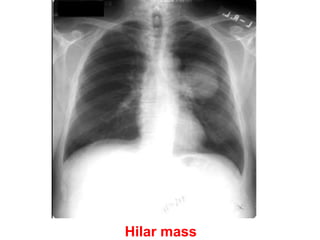

Hilar mass

There is a left hilar mass caused by carcinoma. Pericardial infiltration has

produced effusion and tamponade, evidenced by the severely enlarged

and globular cardiac silhouette. Malignant disease is now the most

common cause of tamponade in most developed countries.